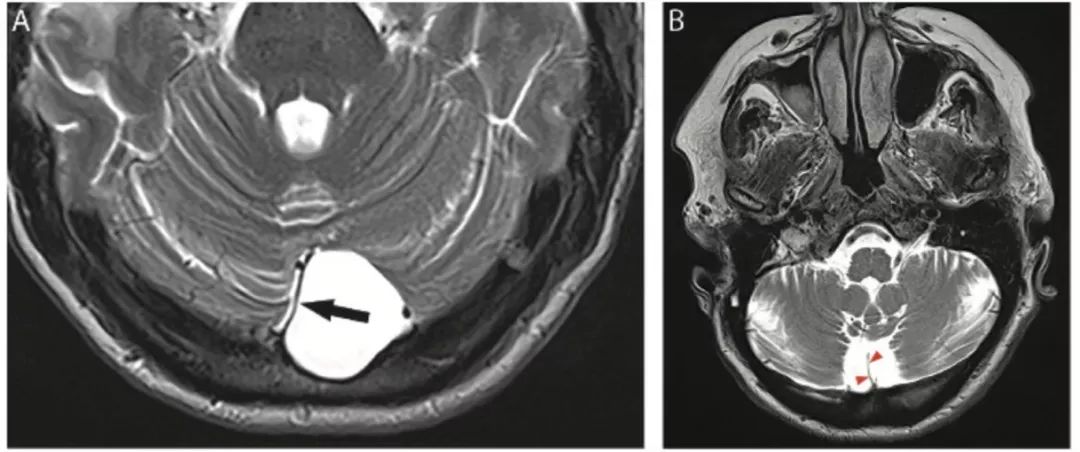

图18 小脑后蛛网膜囊肿与枕大池扩大比较

矢状位较难区分,轴位可见蛛网膜囊肿导致小脑镰(箭头)侧移。枕大池扩大时小脑镰仍位于中线(箭头)。